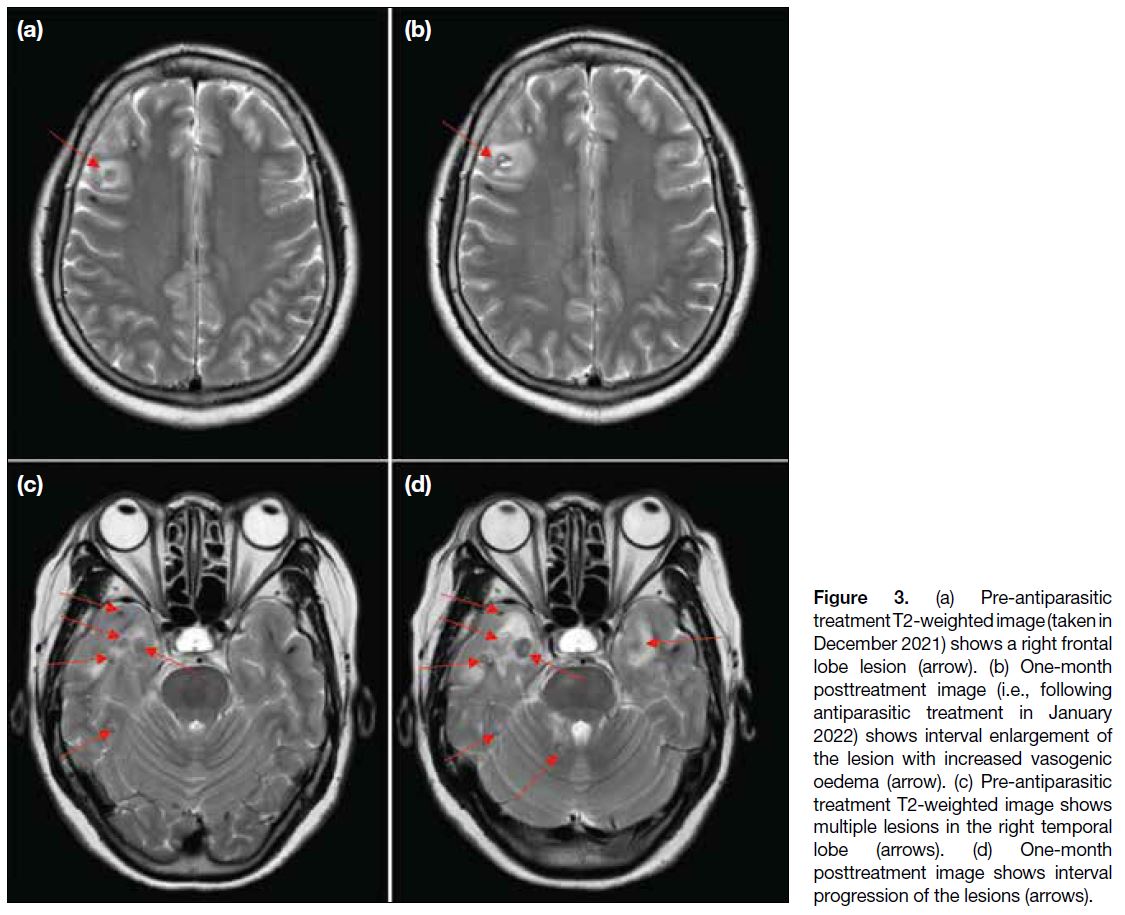

Multiple follow-up MRI scans of the brain were

performed. Initially, at 1-month post-treatment, some

lesions (particularly those at the frontal and temporal lobes) showed interval enlargement with an increase in

perilesional vasogenic oedema (Figure 3). These findings

were thought to be attributable to posttreatment change.

Figure 3. (a) Pre-antiparasitic

treatment T2-weighted image (taken in

December 2021) shows a right frontal

lobe lesion (arrow). (b) One-month

posttreatment image (i.e., following

antiparasitic treatment in January

2022) shows interval enlargement of

the lesion with increased vasogenic

oedema (arrow). (c) Pre-antiparasitic

treatment T2-weighted image shows

multiple lesions in the right temporal

lobe (arrows). (d) One-month

posttreatment image shows interval

progression of the lesions (arrows).